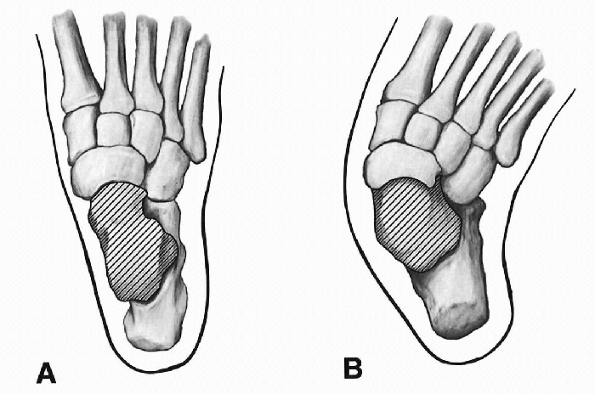

Dorsal dislocation of the talonavicular joint where the navicular lies dorsal to the talus

Osseous changes (Figs. 4.3-1 and 4.3-2)

![]() |

Figure 4.3-1 Osseous changes as viewed from the top. (A) Normal foot. (B)

Foot with vertical talus. (Adapted from Kumar SJ, Cowell HR, Ramsey PL. Foot problems in children. AAOS Instr Course Lect 1982;31:235-251.) |

Figure 4.3-2 Osseous anatomy as seen from a medial view. (A) Normal foot. (B)

Elongated talar neck in congenital vertical talus. (Adapted from Kumar SJ, Cowell HR, Ramsey PL. Foot problems in children. AAOS Instr Course Lect 1982;31:235-251.) |